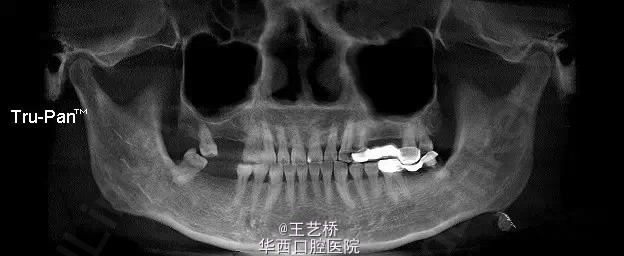

各式各样形态的上颌窦(一)

在进行上颌后牙区种植手术时,上颌窦形态是我们需要考虑吧的重要因素之一。今天收集了众多上颌窦的影像片,供大家交流学习。